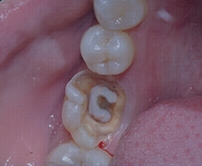

Deep Cavity

Canal Preparation and Disinfection

Open pulp chamber, remove necrotic tissue, then disinfect canals with medicaments.